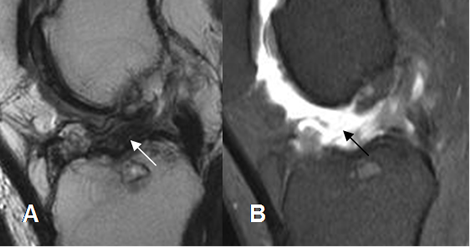

Fig 139. Ruptura parcial del injerto.

A: RM sagital en T2 y B: RM sagital en STIR. Injerto adelgazado, por ruptura parcial.

Fig 140. Ruptura del injerto.

A: RM sagital en T1. No se identifican las fibras del injerto y en su topografía existe tejido de granulación.

B: RM sagital en T2 y C: RM sagital en STIR. Ruptura casi completa del injerto, el cual está rodeado por tejido fibroso.

Fig 141. Ruptura del injerto.

A: RM sagital en T1 y B: RM sagital en STIR. Solución de continuidad del injerto, por ruptura completa.

Fig 142. Ruptura del injerto.

A: RM sagital en T2. Pérdida de la tensión y orientación en las fibras del injerto, sospechando su ruptura.

B: ArtroRM sagital en STIR. Se confirma la ruptura de injerto, con interrupción de sus fibras.